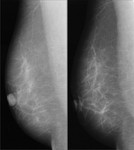

[画像診断]マンモグラフィ画像の合格基準について 2011-03-07

[詳細は「タカ派の画像診断医」へ)